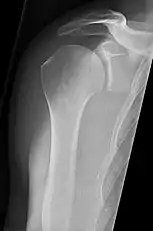

شانهها

تصویر AP سطح اریب خلفی ۴۰ درجه پس از Grashey

بدن باید حدود ۳۰ تا ۴۵درجه نسبت به شانه چرخانده شود تا تصویربرداری انجام شود و بیمار در حالت ایستاده یا نشسته اجازه میدهد دستانش را آویزان کند. این روش شکاف مفصلی و تراز عمودی نسبت به حفرات را نشان میدهد.[16]

_X-ray_of_a_normal_shoulder.jpg.webp)